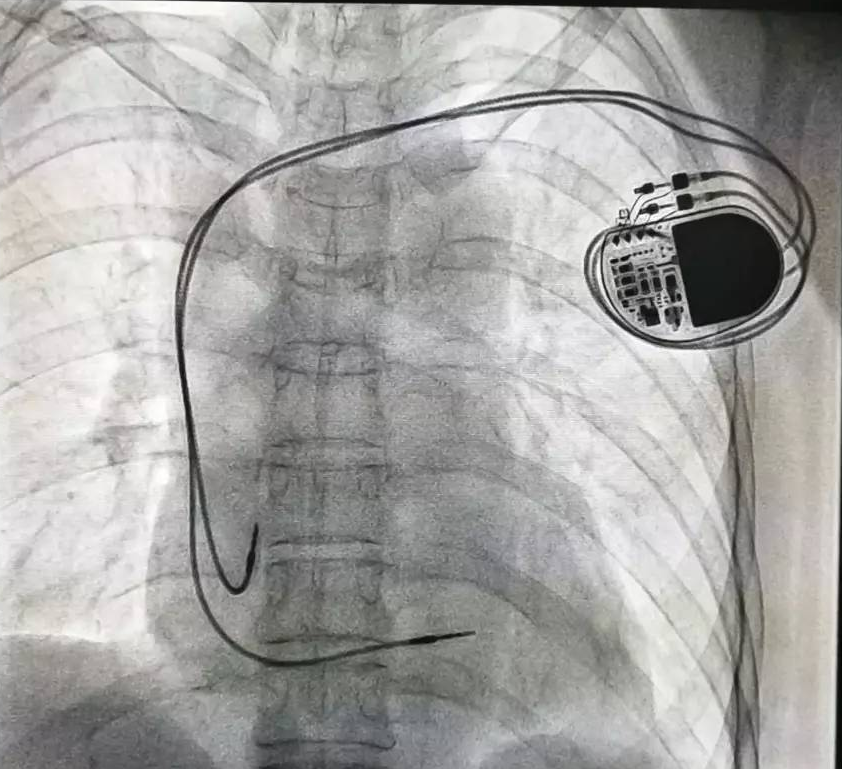

全球唯一!無線雙腔起搏器首次植入

來源:器械之家,未經授權不得以任何形式轉載,且24小時后方可轉載。2022年2月7日雅培宣布,其在研型Aveir?雙腔無引線起搏器完成了全球首例患者植入,這也是全世界第一個雙腔無線起搏器。Aveir?DR雙腔起搏器提供右心房和心臟右心室的同步、逐次跳起搏,近80%接受起搏器治療的患者需要雙腔選擇,A